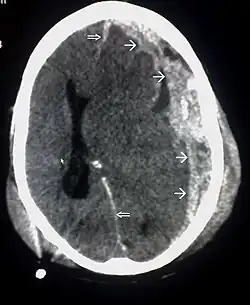

CT scan showing cerebral contusions, hemorrhage within the hemispheres, and subdural hematoma. There is also displaced skull fracture of left transverse parietal and temporal bones.[2] | |

One type of focal injury, cerebral laceration, occurs when the tissue is cut or torn.[37] Such tearing is common in orbitofrontal cortex in particular, because of bony protrusions on the interior skull ridge above the eyes.[31] In a similar injury, cerebral contusion (bruising of brain tissue), blood is mixed among tissue.[23] In contrast, intracranial hemorrhage involves bleeding that is not mixed with tissue.[37]

Hematomas, also focal lesions, are collections of blood in or around the brain that can result from hemorrhage.[11] Intracerebral hemorrhage, with bleeding in the brain tissue itself, is an intra-axial lesion. Extra-axial lesions include epidural hematoma, subdural hematoma, subarachnoid hemorrhage, and intraventricular hemorrhage.[38] Epidural hematoma involves bleeding into the area between the skull and the dura mater, the outermost of the three membranes surrounding the brain.[11] In subdural hematoma, bleeding occurs between the dura and the arachnoid mater.[23] Subarachnoid hemorrhage involves bleeding into the space between the arachnoid membrane and the pia mater.[23] Intraventricular hemorrhage occurs when there is bleeding in the ventricles.[38]